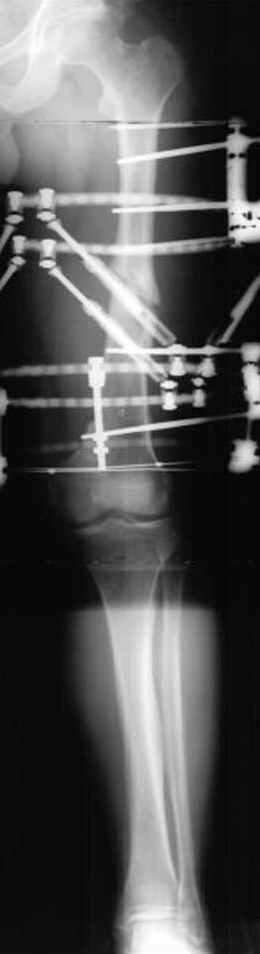

Отправитель: Djoldas Kuldjanov 23 Ноябрь 2004, 18:21

пластическая модель; и коррекция бедра аппаратом Илизарова.

Имею другие снимки тоже, получится как отчет о моей работе.

Отправитель: Evgueny Tschekashkin 24 Ноябрь 2004, 21:09

хотя даже если бы и инфекция , то nail exchange с рассверливанием канала - вариант дебрайдмента) Я думаю, что последовательность развития событий:

Узкий к-м канал - тонкий гвоздь- усталостный перелом дистальных винтов - развитие нестабильности и как ее результат остеолиз вокруг гвоздя - деформация анатомической оси бедра. Похоже, что я понял почему аппарат, а не новый гвоздь:-)

ЕТ - Изначально костно-мозговой канал бедра был узкий, дальнейшее его рассверливание ещё больше скомпрометирует прочность бедра( латеральный кортекс дистального отломка уже истончен), приведет к дефекту наружной стенки - хотя это только мои догадки - хотелось бы знать мнение Джолдаса о выбранной тактике.